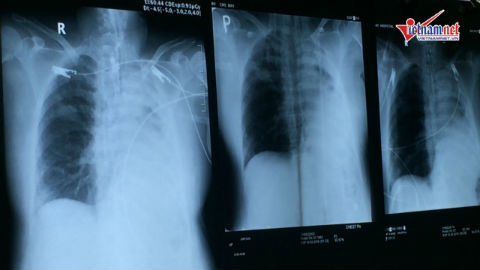

Với 15.000 - 20.000 lượt người ra vào Bệnh viện Chợ Rẫy mỗi ngày, việc phòng chống cúm A H1N1 tại đây gặp nhiều khó khăn.